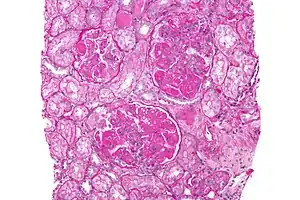

| Micrograph of diffuse proliferative lupus nephritis showing increased mesangial matrix and mesangial hypercellularity. Kidney biopsy. PAS stain. | |